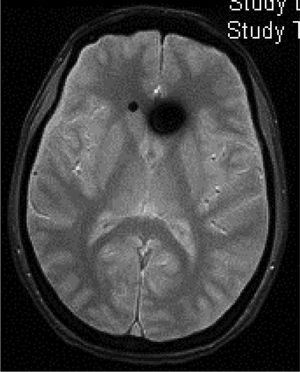

Head CT: findings are usually normal, although some studies have reported engorged venous sinuses, small ventricles, subdural fluid collections (Fig. 4), obliteration of the prepontine cistern, and images of pseudosubarachnoid haemorrhage (hyperdensity of the tentorium and Sylvian fissure).49

Diffuse pachymeningeal enhancement (73–80%), which is also observed on non-contrast FLAIR sequences in the majority of cases (Fig. 2)Extra-axial fluid collections (35–50%), hygromas in 60% of cases and haematomas in 40% (Fig. 4) Brain sagging disproportionate to the size of the fluid collections (43%). Images may display the following signs:Ventricular collapseBowing of the optic chiasm Flattening of the pons against the clivus with obliteration of the pontine cistern Drooping of the corpus callosumDescent of the cerebellar tonsilsVenous engorgement (57%) Enlarged pituitary gland (38%)Intraventricular pneumocephalus (Fig. 5) in cases of iatrogenic SIHDecreased optic nerve diameter and thickness on coronal T2-weighted sequences, also detectable with transorbital ultrasound SIH: spontaneous intracranial hypotension.

Figure 4.Subdural fluid collection (subdural haematoma) in the parieto-occipital convexity of a 46-year-old man with spontaneous intracranial hypotension following spinal anaesthesia administered for knee surgery. Courtesy of Dr. Belvís. Neurology department, Hospital de la Santa Creu i Sant Pau. Barcelona.